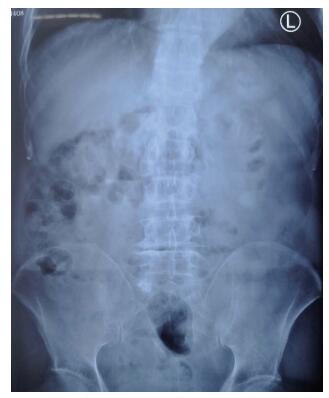

二、实验室及辅助检查血常规示白细胞14.25×109/L,中性粒细胞0.883,红细胞4.25×1012/L,血红蛋白133 g/L,血小板249×109/L。降钙素原0.44 ng/ml,CRP 59.5 mg/L,超敏CRP > 5 mg/mL。凝血检测:凝血酶原时间11.2 s,活化部分凝血酶原时间25.3 s,纤维蛋白原含量2.41 g/L,凝血酶时间11.0 s。尿常规、肝肾功能正常。抗O、RF、CCP(-)。双膝关节正侧位片无异常。腹部立位片示腹部肠管内见少量气体及肠内容物,中腹部可见小气液平面(图 1)。全腹CT示小肠肠管聚拢,肠管增宽,宽4.0 m,肝脏、胆囊、胰腺、脾脏未见异常(图 2)。

图 2 一例腹型过敏性紫癜患者全腹CT |